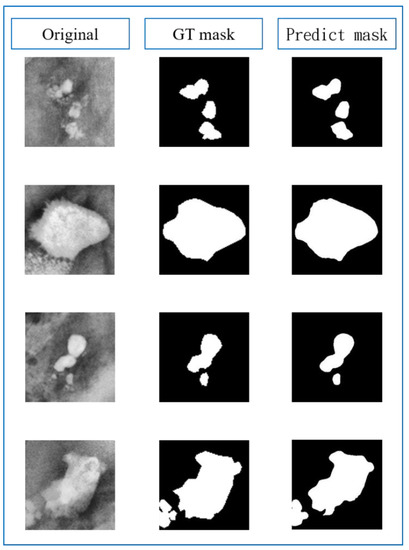

3.4. Subsystem 2—Segmentation Model for Medical Images